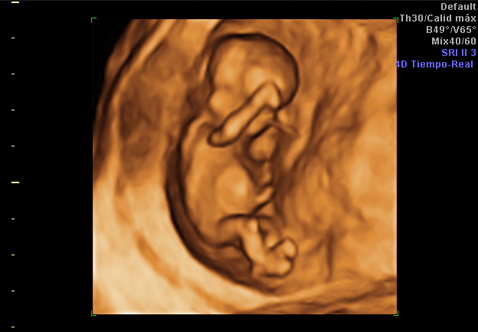

Así como una ecografía en dos dimensiones recoge imágenes de cortes o secciones del feto, la de tres dimensiones une cientos de estas secciones para reconstruir la superficie externa del feto. Para que se entienda, es como si unimos todas las rebanadas de una hogaza de pan para obtener su forma original.

Porque a las tres espaciales unimos el tiempo. Es decir, la ecografía 4D consiste en ver imágenes en 3D junto con sus movimientos a tiempo real, de manera que podemos visualizar el exterior del feto moviéndose.

Aunque se puede realizar en cualquier momento, para ver satisfactoriamente la cara fetal es recomendable realizarla alrededor de la semana 28 de la gestación, que es cuando el feto tiene las facciones más parecidas a las de un recién nacido; además, en este momento es cuando se tiene una cantidad óptima de líquido amniótico.

Este líquido es que permite la transmisión de las ondas, por lo que si se encuentra disminuido las ondas de ultrasonidos no se transmiten adecuadamente y la imagen será peor. Lo mismo ocurre si se utilizan cremas de alto contenido graso o en pacientes con un panículo adiposo grueso en el abdomen.